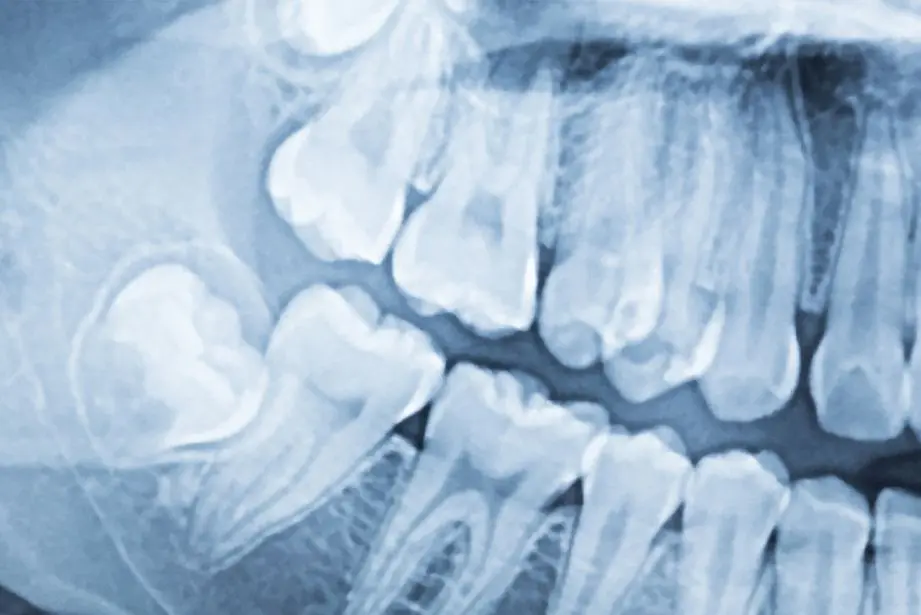

Zakaj potrebujete rentgenski in/ali CT posnetek?

Včasih nam samo pregled ustne votline ne pove vsega, kar moramo vedeti. Pogosto lahko tisto, kar je vidno, vara, resnična težava pa se lahko skriva pod dlesnimi, globoko v zobnih strukturah ali v sami čeljusti. 2D in 3D rentgenska diagnostika ne pušča prostora za napačne presoje in daje pravo sliko pacientovega zobozdravstvenega stanja.

Ortopan ali rentgenski pregled zob je panoramska slika zob, ki prikazuje trenutno stanje ustne votline in se naredi pred katerim koli zobozdravstvenim posegom. Ortopan in CT slikanje sta še posebej pomembna pri načrtovanju postopkov implantacije in operacij na splošno.